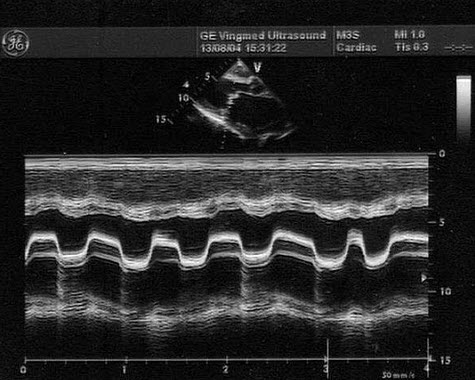

100、单项选择题

该病例最可能的诊断()

A.主动脉窦瘤

B.主动脉瓣脱垂

C.主动脉瓣下狭窄

D.主动脉瓣畸形

E.以上都不是